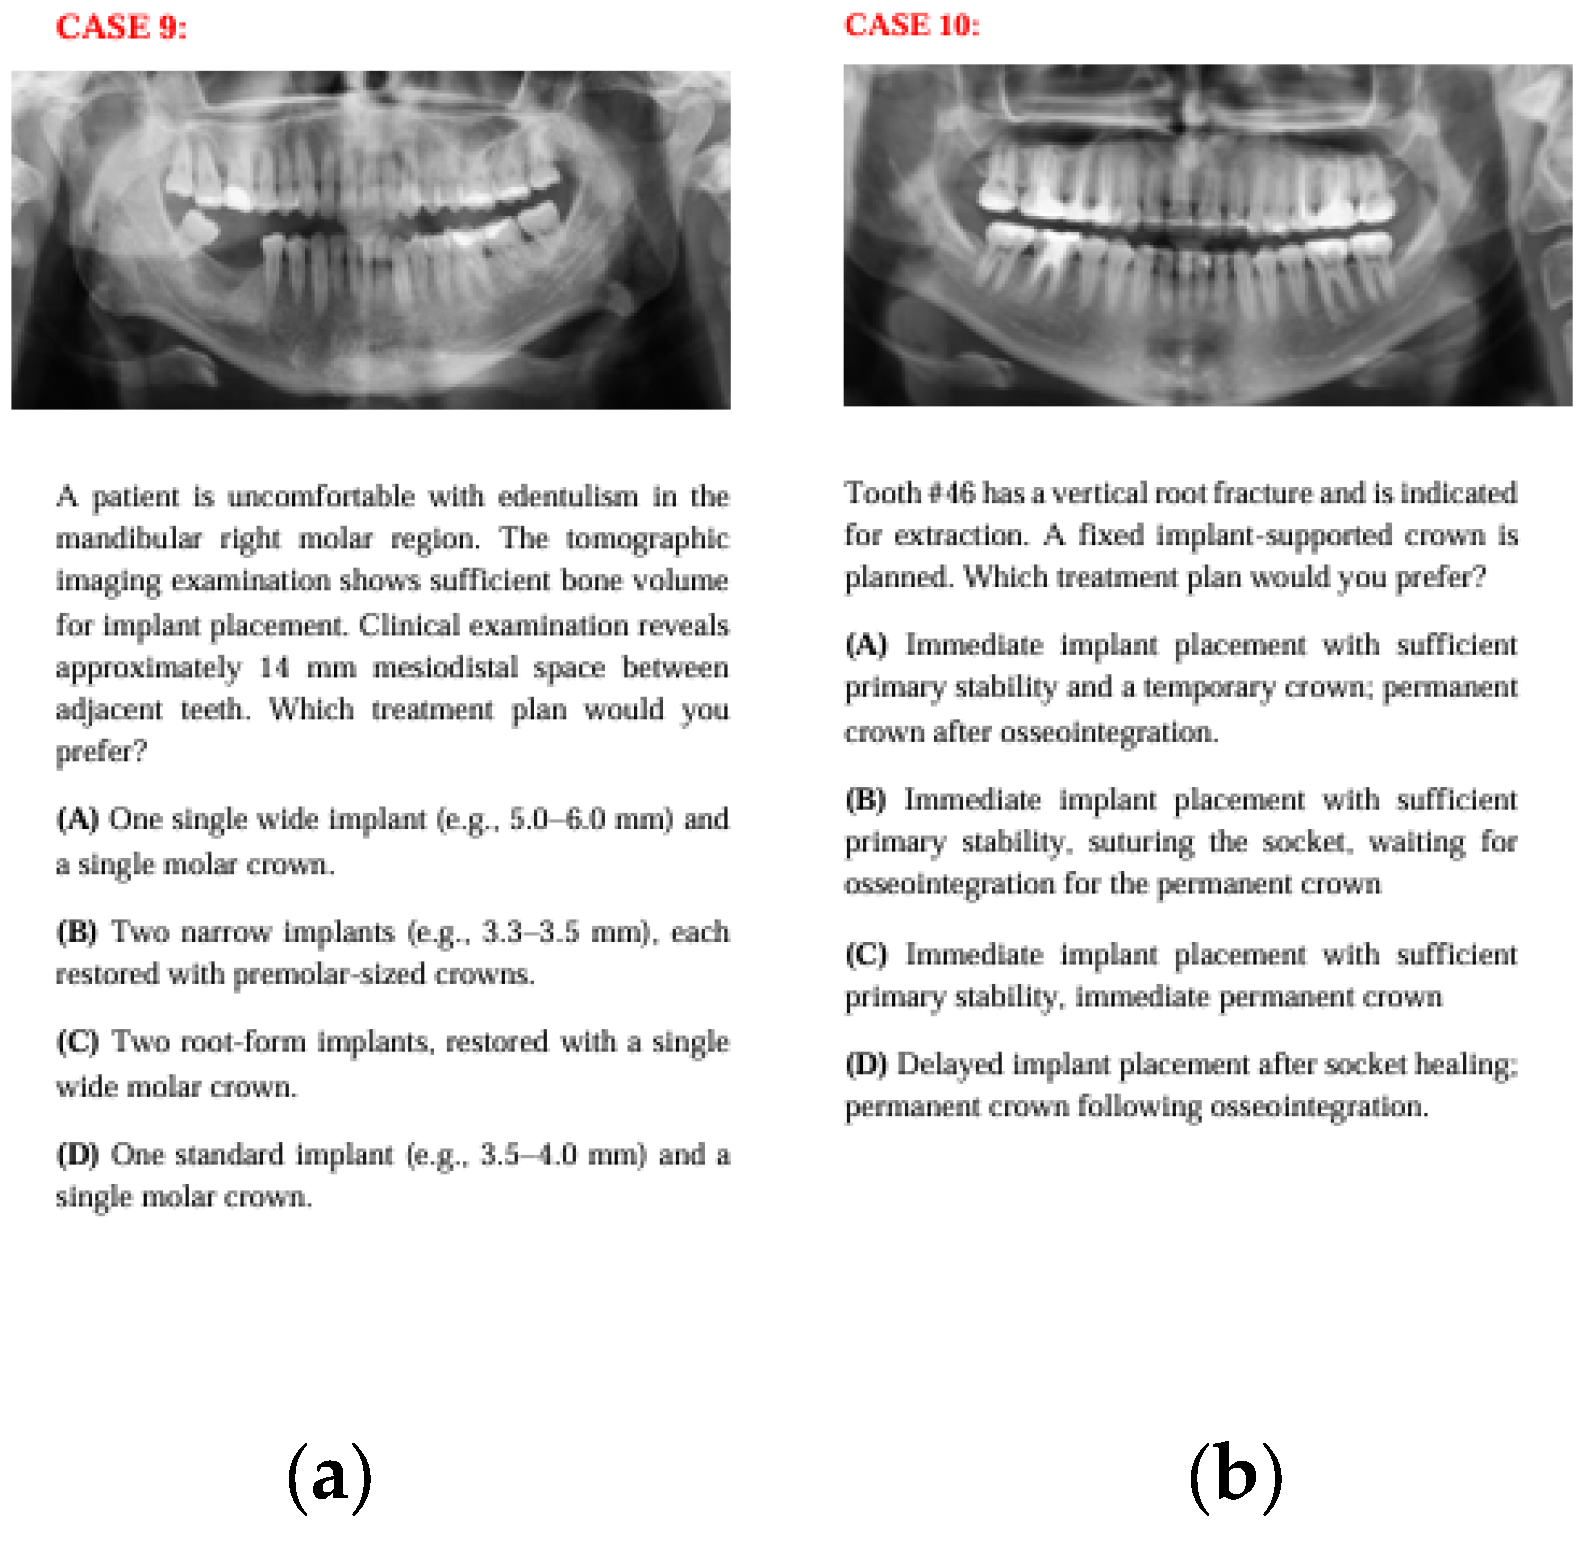

2.2. Case Scenario Preparation

Fourteen anonymized real patient cases with pre-implant surgery panoramic images were selected for the study. 14 cases were selected retrospectively from the patient records of the Department of Prosthodontics at Ankara University. The selection was performed jointly by one prosthodontist and one oral surgeon, based on representations of common clinical scenarios in implantology from simpler cases to more complex cases (single tooth loss, partial edentulism, and full-arch cases). Cases with poor radiographic quality, systemic contraindications, or unclear treatment history were excluded. To facilitate responses from both clinicians and the AI model, tomographic data, interocclusal distance, and other relevant surgical and prosthetic information were provided in written form, while only panoramic radiographs were presented visually. Due to the very large file sizes of cone-beam computed tomography (CBCT) datasets, which exceeded the upload limits, CBCT images were not provided; however, all clinically relevant three-dimensional information obtainable from CBCT was summarized within the case descriptions to ensure sufficient data for treatment planning. It was assumed that all patients mentioned in the case scenarios had good systemic health, adequate oral hygiene, and no financial restrictions for standardization. Clinical scenarios were prepared with four alternative treatment options for each case. The four management options for each case were drafted by one senior prosthodontist and one oral surgeon with >10 years of experience. The options were reviewed for clinical plausibility and to ensure that at least two alternatives represented commonly accepted approaches, while others reflected less preferred yet still clinically possible options (not intentionally wrong or contraindicated). The aim was not to distinguish “correct vs. incorrect” answers but to evaluate preference tendencies between clinicians and AI when faced with multiple feasible solutions. Scenarios included surgical parameters such as the number, size, location, and position of implants, the need for additional surgical procedures, and the placement protocol, as well as prosthetic factors including prosthesis type and number, location, abutment selection, material preferences, and loading protocols. Prosthetic and surgical considerations varied for each question. The panoramic radiographs, along with the case descriptions and four treatment options, are presented in Figure 1, Figure 2, Figure 3, Figure 4, Figure 5, Figure 6 and Figure 7.

Figure 5. The panoramic radiographs, descriptions, and four treatment options of Case 9 (a) and Case 10 (b).

In Case 10, although all three groups predominantly recommended immediate loading (option A), some clinicians also preferred delayed loading (option B), which led to a statistically significant distribution difference. In this case, AI may have recommended immediate loading based on primary stability criteria in the literature, while clinicians considered the risks of biological complications and opted for more traditional loading protocols. This reflects the differing priorities among groups in the clinical decision-making process.

In Case 11, where the case involved anterior esthetics and immediate implantation, clinicians predominantly chose options C and D, while AI chose option A. This may be because clinicians aimed to avoid the risk of placing implants across the entire area in an anterior region with a history of lesions or, guided by clinical intuition, leaned toward treatments with fewer implants or plans like option D that involve waiting for osseointegration to reduce complications. AI, on the other hand, may have leaned toward option A, which aligns with the current literature emphasizing the success of immediate implantation with immediate provisional prostheses in the esthetic zone, aiming to place as many implants as possible.